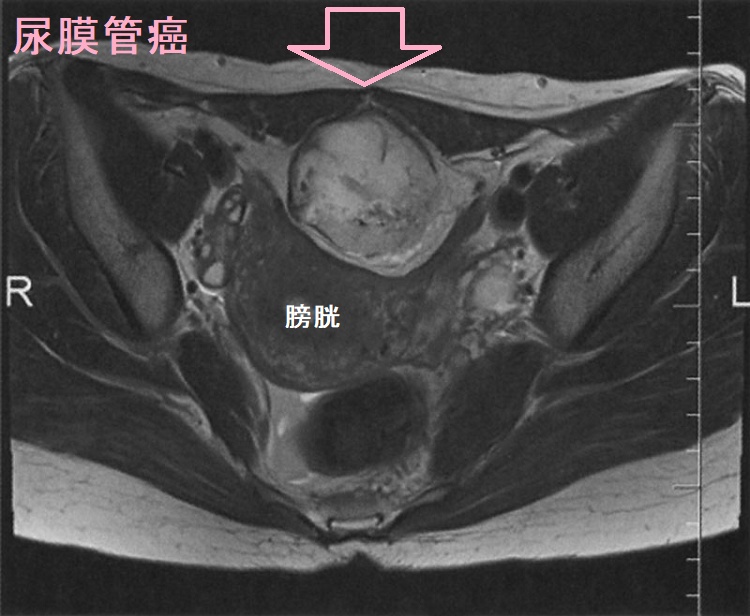

尿膜管遺残(尿膜管嚢胞)は、尿膜管癌になる場合もあります。尿膜管癌は膀胱粘膜下腫瘤で、頻尿症状などから見つかります。